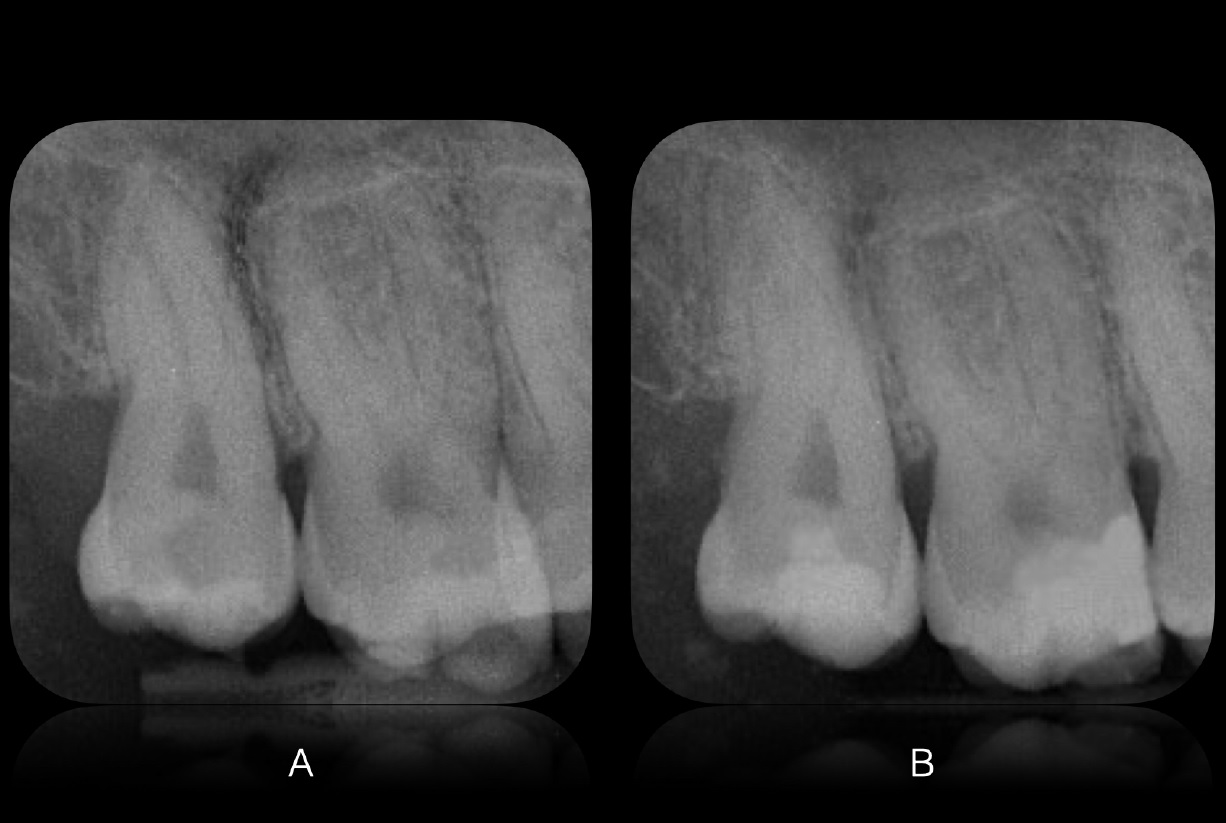

Εικ. 1: Ασθενής 21 ετών προσήλθε στην κλινική με ευαισθησία στο κρύο στο άνω δεξιό τεταρτημόριο. Η ενδοστοματική κλινική εξέταση αποκάλυψε μια παλιά, αποκατάσταση σύνθετης ρητίνης στον δεύτερο άνω γομφίο με ρωγμές και τερηδόνα στον τρίτο γομφίο. Η ακτινογραφία επιβεβαίωσε μια βαθιά τερηδονική αλλοίωση στον τρίτο γομφίο και την παρουσία μιας κατεστραμμένης αποκατάστασης σύνθετης ρητίνης στον δεύτερο γομφίο.

Εικ. 18: Ακτινογραφική αξιολόγηση: (Α) Πριν την αποκατάσταση, (Β) Μετά από επανέλεγχο τριών μηνών.